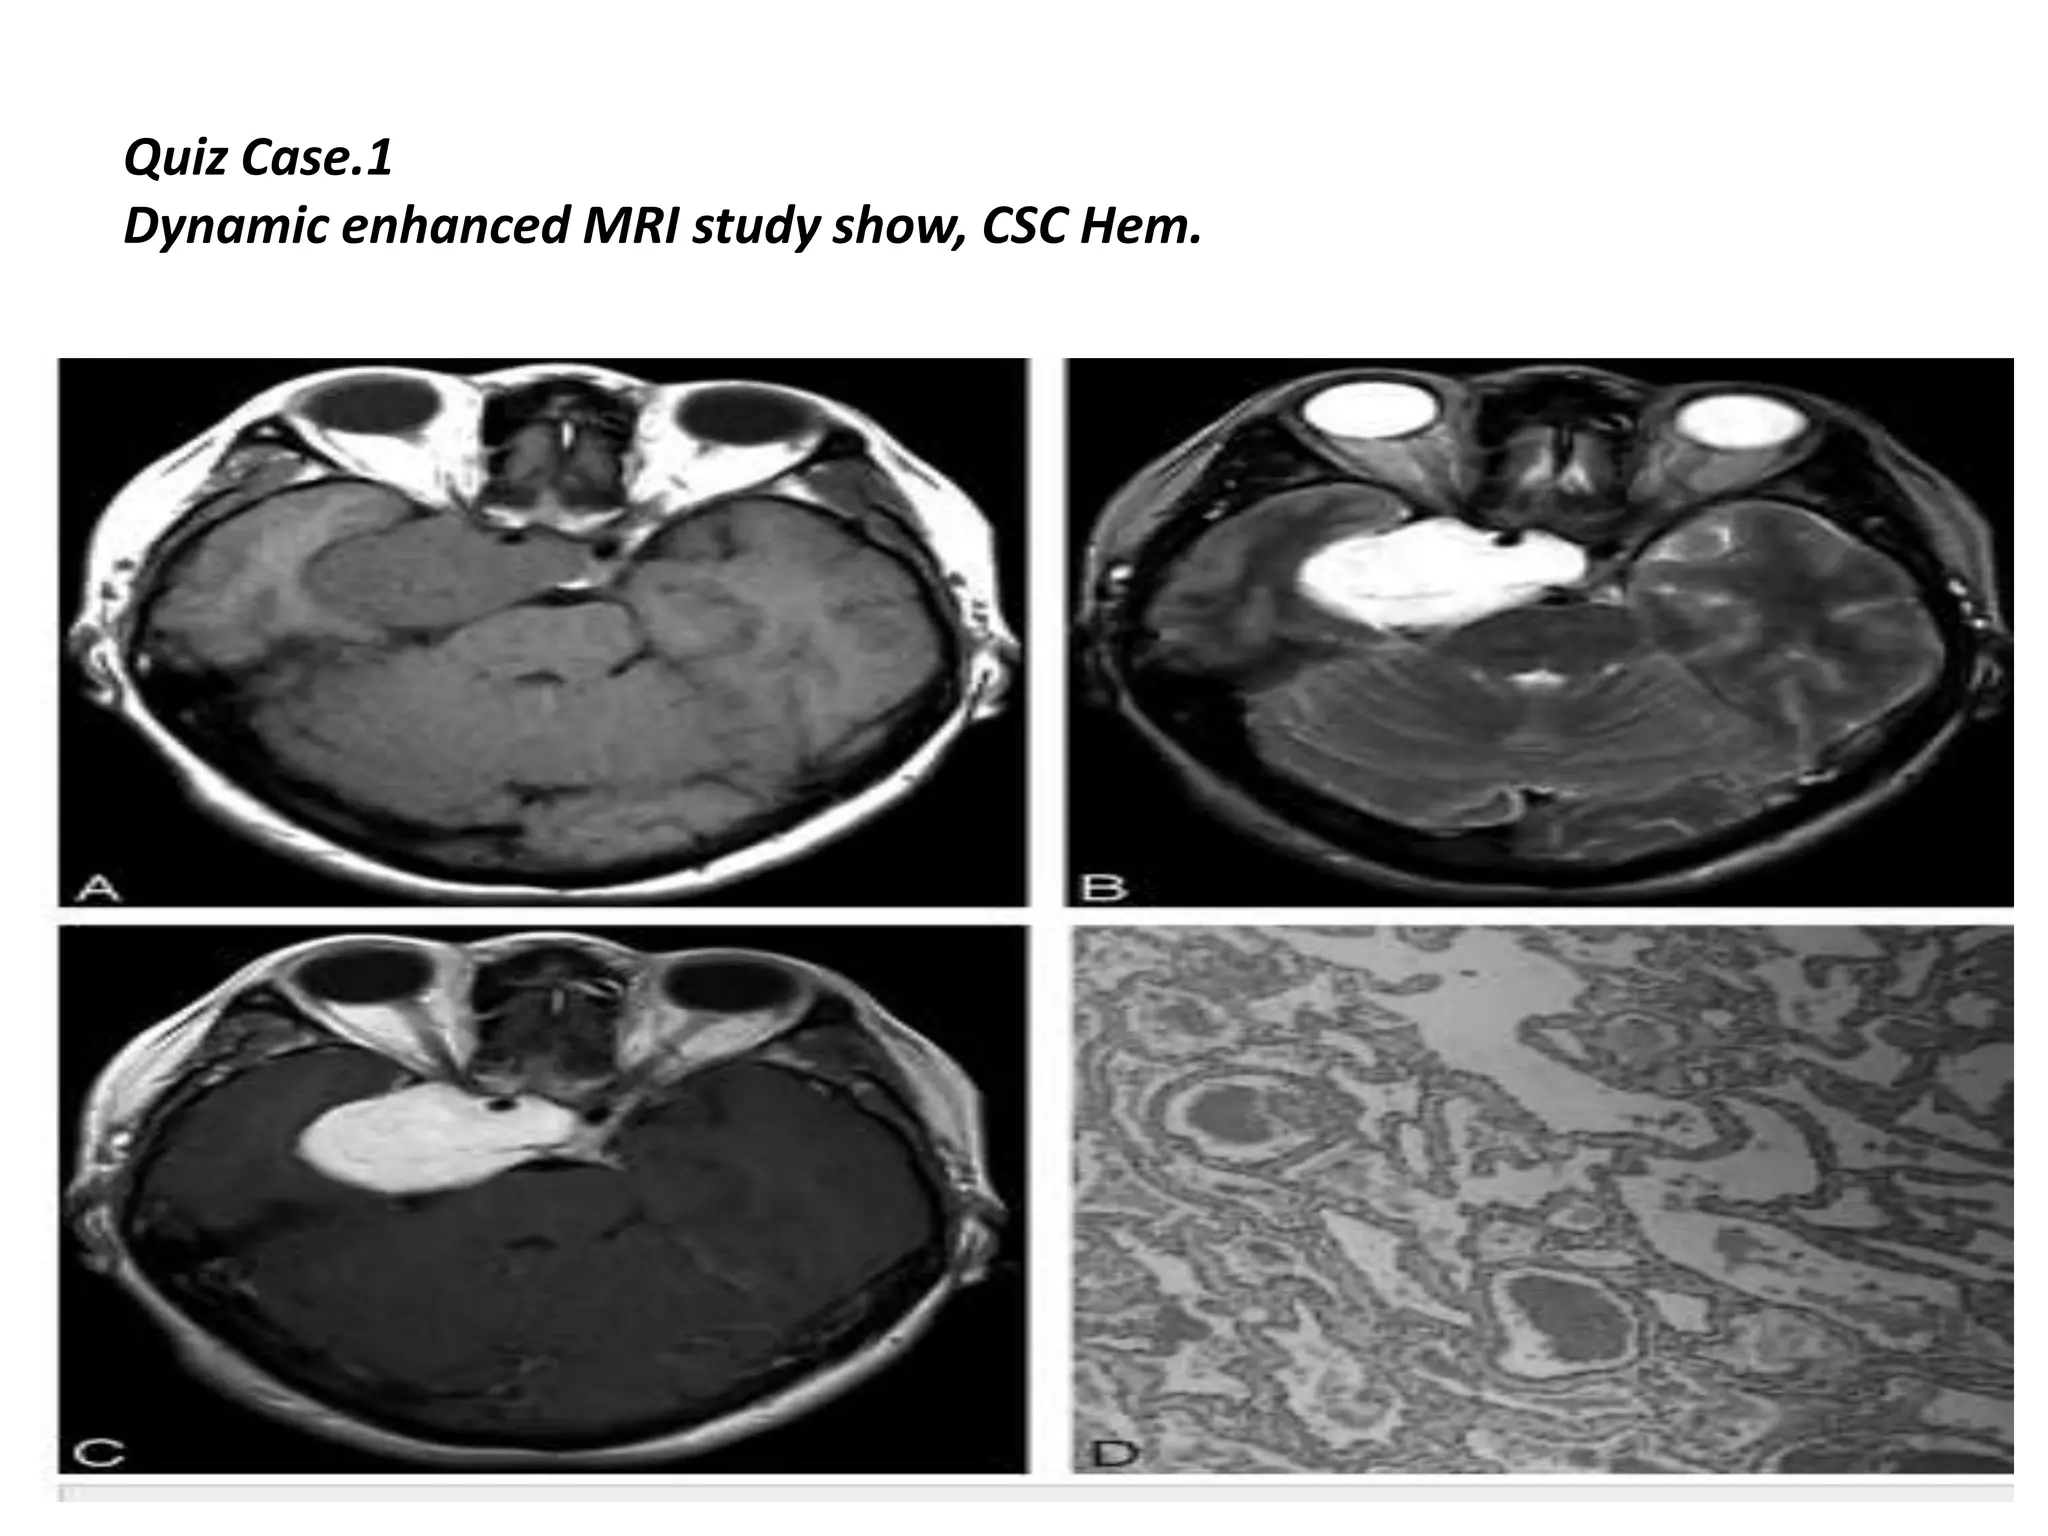

Quiz Case.1

Dynamic enhanced MRI study show, CSC Hem.